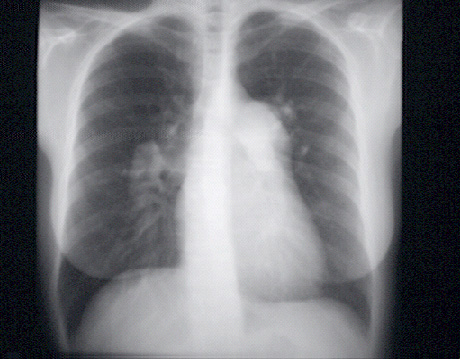

These chest X rays show a markedly dilated pulmonary artery.

In this PA view, it is demonstrated just beneath the aortic knob at the upper left sternal border. Note that the dilated pulmonary artery tapers rapidly. This has been called “pruning” and is typical of severe pulmonary hypertension.